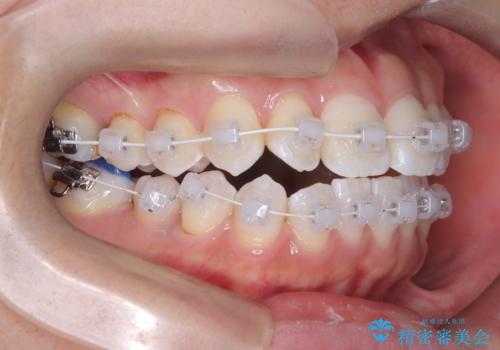

治療は、白いコーティングが施されたワイヤーを使用した審美性の高い装置にて行っています。

本症例では、治療の途中で**バイトアップ(咬み合わせを一時的に挙上する処置)**を行い、

上下の歯が干渉しない環境を作りながら、捻転や叢生の改善を進めました。

これにより、歯を無理に動かすことなく、効率的かつ安全に歯列を整えることが可能となります。

装置には、ワイヤーに白いコーティングが施された審美性の高いワイヤー矯正装置を使用し、

治療中も目立ちにくい配慮を行いました。